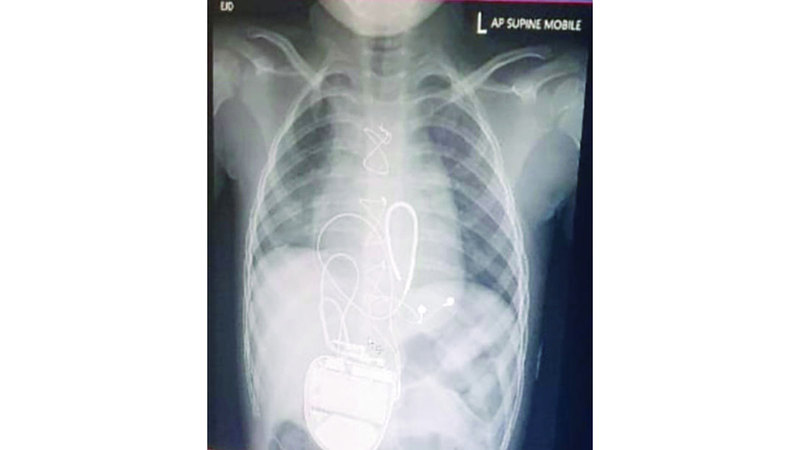

وكانت (مريم) خضعت لعملية جراحية لتركيب جهاز مقوم، منظم للقلب ومزيل للرجفان، في مستشفى الجليلة التخصصي للأطفال.

وقال: «أكد لي الأطباء أنها تعاني مرض الورم العضلي المخطط، أو ما يسمى (ربدومايلوما)، وأنها تحتاج إلى عملية جراحية في القلب لتركيب جهاز يسمى مقوم ومنظّم القلب ومزيل الرجفان القابل للزراعة، لمنع إصابتها بالسكتات القلبية المفاجئة».

وتابع: «نقلتها إلى مستشفى الجليلة التخصصي للأطفال، حيث خضعت لعملية جراحية، وكان هذا بالغ الأهمية لها، لأن عدم إجراء العملية كان سيعرّضها لسكتة قلبية قاتلة».